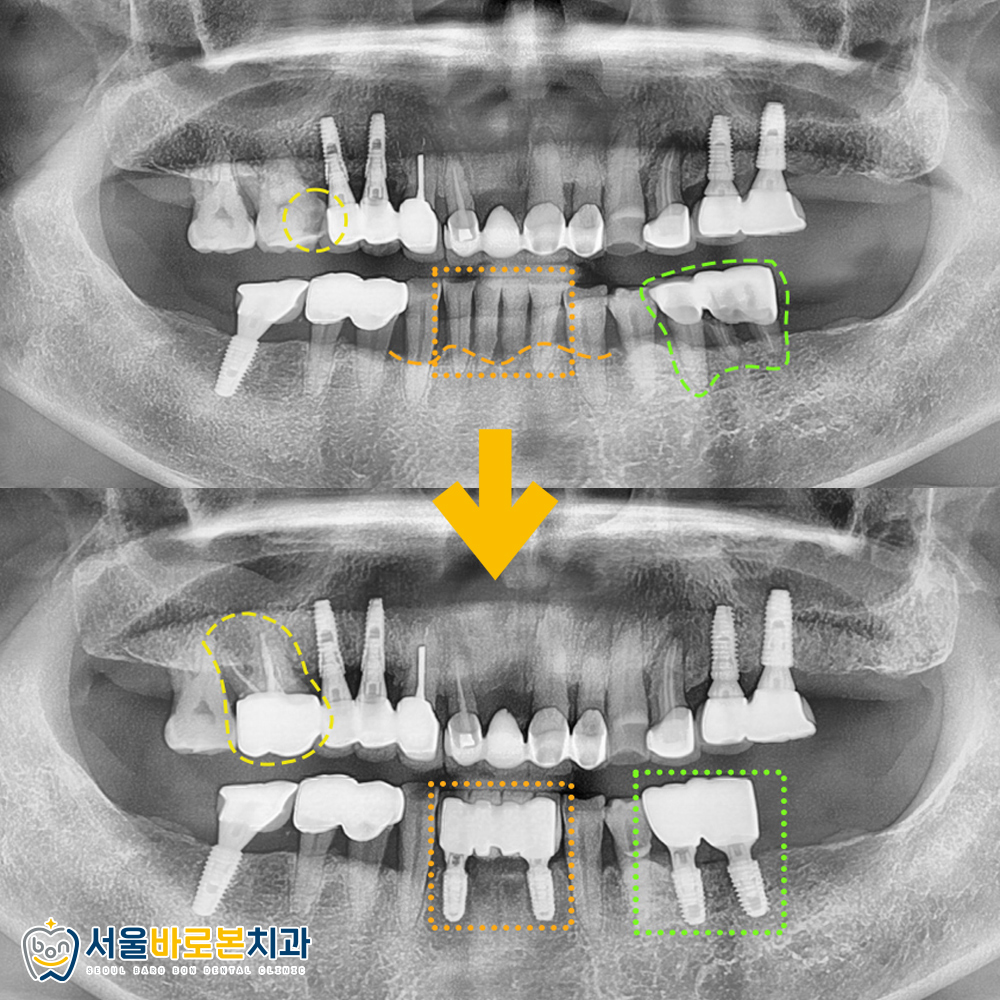

🔹 오른 쪽 위 어금니에

구멍이 있어서 시리고 (노란색)

🔹 왼쪽 아래 어금니에 흔들림이 (연두색)

있다고 말씀해주셨습니다.

🔹 또한 임플란트 상담을

원하신다는 아래 앞니는 (주황색)

흔들림이 심한 상태였습니다.

파노라마 사진을 촬영해 확인해보았습니다!

* X-ray 사진상으로 보이는

오른쪽이 실제로는 왼쪽이므로

참고하여 봐주시길 바랍니다.

1) 우선 임플란트 상담을 원하신다는

아래쪽 앞니 치아를 보시면 (주황색)

잇몸뼈가 심하게 내려앉아

흔들림이 심한 상황이었는데요.

주황색 네모 박스 밑에

점선으로 표시한 부분이 잇몸뼈의 높이인데,

치아 뿌리 부근까지 잇몸뼈가 녹아

간신히 치아를 지탱하고 있었습니다.

2) 연두색 표시의 아래 어금니들은

과거 크라운 치료를 받은 상태인데

파절이 되어 흔들림이 있었는데요.

주황색과 연두색 표시의 치아들은

예후가 너무 좋지 않아

발치가 필요하였답니다.

우선 앞니 총4개, 어금니 2개를 발치하고

임플란트를 식립했습니다.